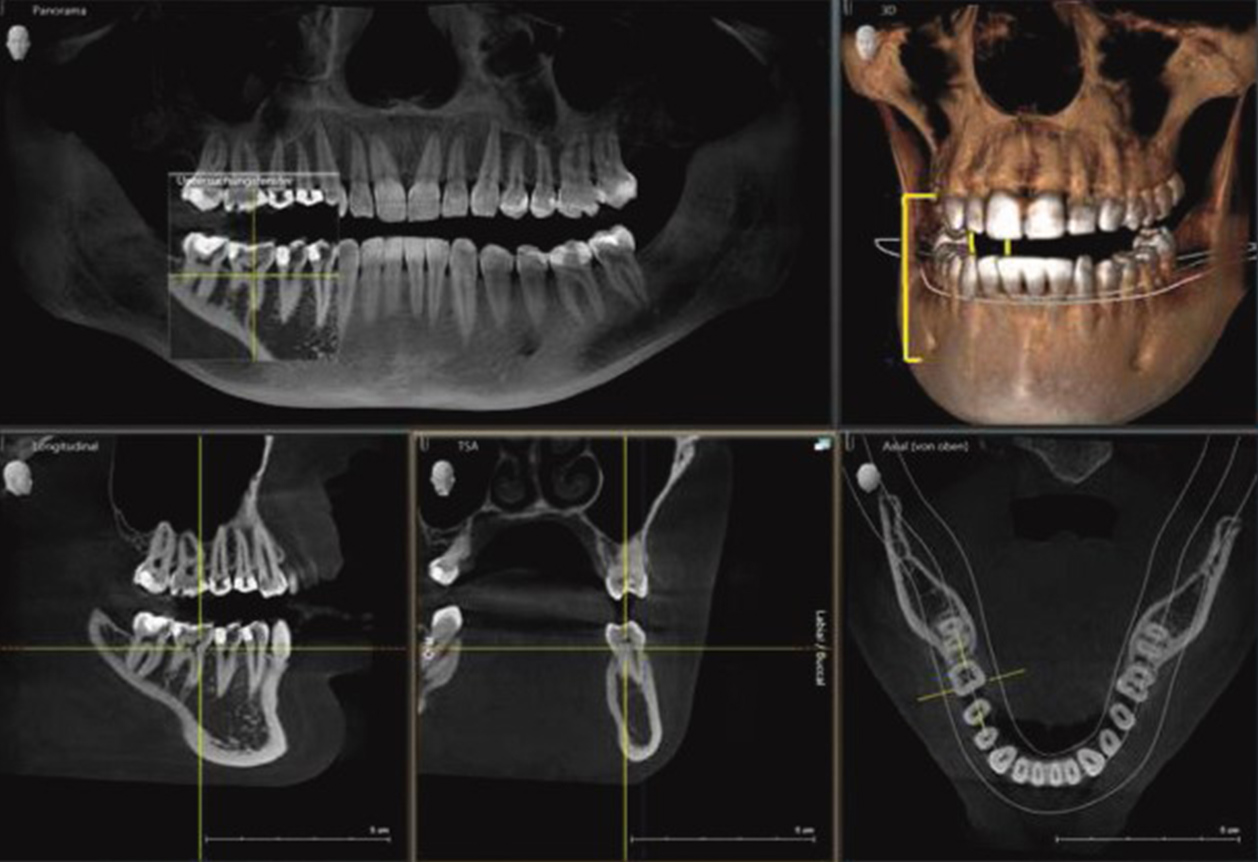

Die digitale Volumentomographie (DVT) ist ein fortschrittliches bildgebendes und strahlungsarmes radiologisches Verfahren, das speziell für die präzise Darstellung der Kiefer- und Zahnstruktur entwickelt wurde und hochauflösende Röntgenbilder und eine exakte 3D-Ansicht des Schädels erzeugt. Im Gegensatz zur herkömmlichen zweidimensionalen Röntgentechnik ermöglicht das strahlungsarme DVT-Röntgenverfahren eine dreidimensionale Visualisierung von Zähnen und Kiefern, was eine detaillierte Bildgebung der anatomischen Strukturen sowie der genauen Lagebeziehungen erlaubt. Das vorhandene Knochenvolumen, die Nasennebenhöhlen, kleinste Weichteilstrukturen sowie die genaue Position der Nervenbahnen werden dabei ohne Vergrößerung oder Verzerrung dreidimensional dargestellt.

Dies bildet zum einen die Grundlage für eine umfassende und präzise 3D-Röntgendiagnostik und ermöglicht zum anderen die optimale Planung verschiedener Behandlungen und kieferchirurgischer Eingriffe, wie sie in der Zahnarztpraxis Dr. Zieger in Bonn durchgeführt werden.

Ein entscheidender Vorteil der digitalen Volumen­tomographie (DVT) ist zudem die

enorme Reduzierung der Strahlenbelastung im Vergleich zur konventionellen Röntgentechnologie eines Standard-CTs bei gleichzeitigem Gewinn maximaler Informationen für eine präzise Röntgendiagnose. Aus diesen Gründen kommt die digitale Volumen­tomographie (DVT) in vielen Bereichen der Zahnmedizin zum Einsatz:

Quelle: Dentsply Sirona

Bei der zahnärztlichen Implantologie ermöglicht die dreidimensionale digitale Volumentomographie (DVT) beim Setzen von Zahnimplantaten eine besonders präzise 3D‑Diagnostik und 3D‑Planung. Die DVT liefert dabei entscheidende Informationen für die Bestimmung des vorhandenen Knochenangebots im Rahmen einer digitalen 3D‑Implantatplanung am PC, wodurch eine exakte Positionierung des Zahnimplantats im Kiefer erfolgen kann. So können in der Implantatprothetik anatomisch wichtige Strukturen wie Kieferknochen, Kieferhöhlen, Nervenverläufe und Nervenaustrittspunkte präzise dargestellt und bei der Planung von Zahnimplantaten und implantatprothetischen Versorgungen (implantatgetragener Zahnersatz) berücksichtigt werden. Auf der Grundlage des 3D‑Röntgens kann so die gesamte Implantation vorab sicher geplant werden, sodass das Operationsrisiko, insbesondere bei schwierigen Fällen mit komplizierten Knochenverhältnisse und starkem Knochenrückgang, deutlich minimiert wird.